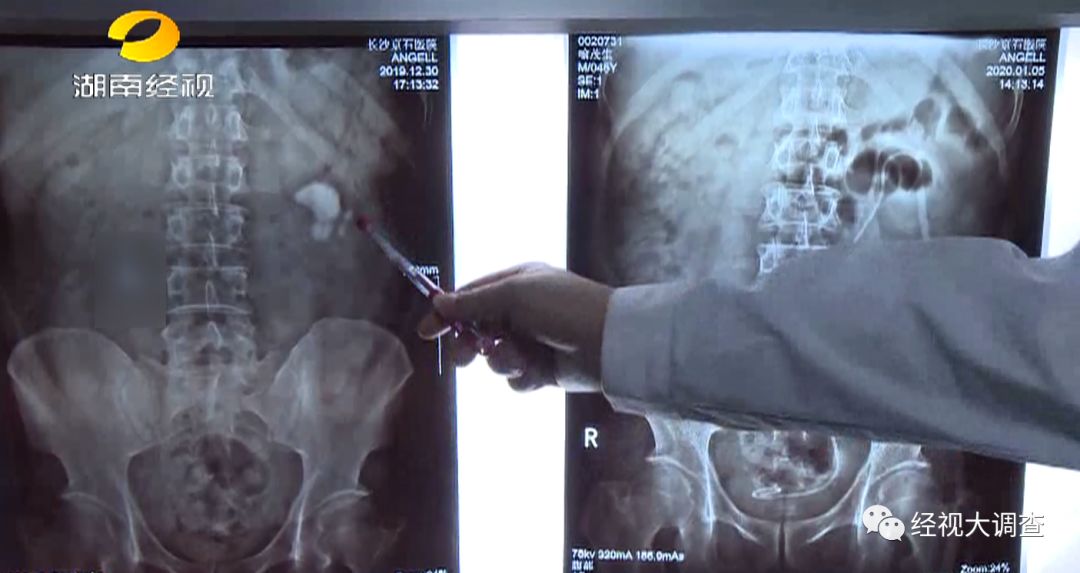

4公分結(jié)石形似蘑菇

今年46歲的喻先生,在安化老家從事瓷磚銷售生意。2012年,喻先生曾患有泌尿結(jié)石,當(dāng)時(shí)通過(guò)體外碎石僅治療了輸尿管下段結(jié)石。對(duì)于腎結(jié)石,他采取了保守療法。本以為結(jié)石會(huì)就此痊愈,沒想多年底業(yè)務(wù)量增多,經(jīng)常要裝卸瓷磚,體力活動(dòng)量大,出汗多喝水少,竟讓結(jié)石又卷土重來(lái)。

掌握喻先生的病情后,通過(guò)雙鏡聯(lián)合微創(chuàng)保腎取石術(shù)一次性清除了左腎內(nèi)多發(fā)性結(jié)石。喻先生表示把反復(fù)折騰自己的腎結(jié)石治好了,終于可以輕輕松松回家過(guò)個(gè)安心年了。